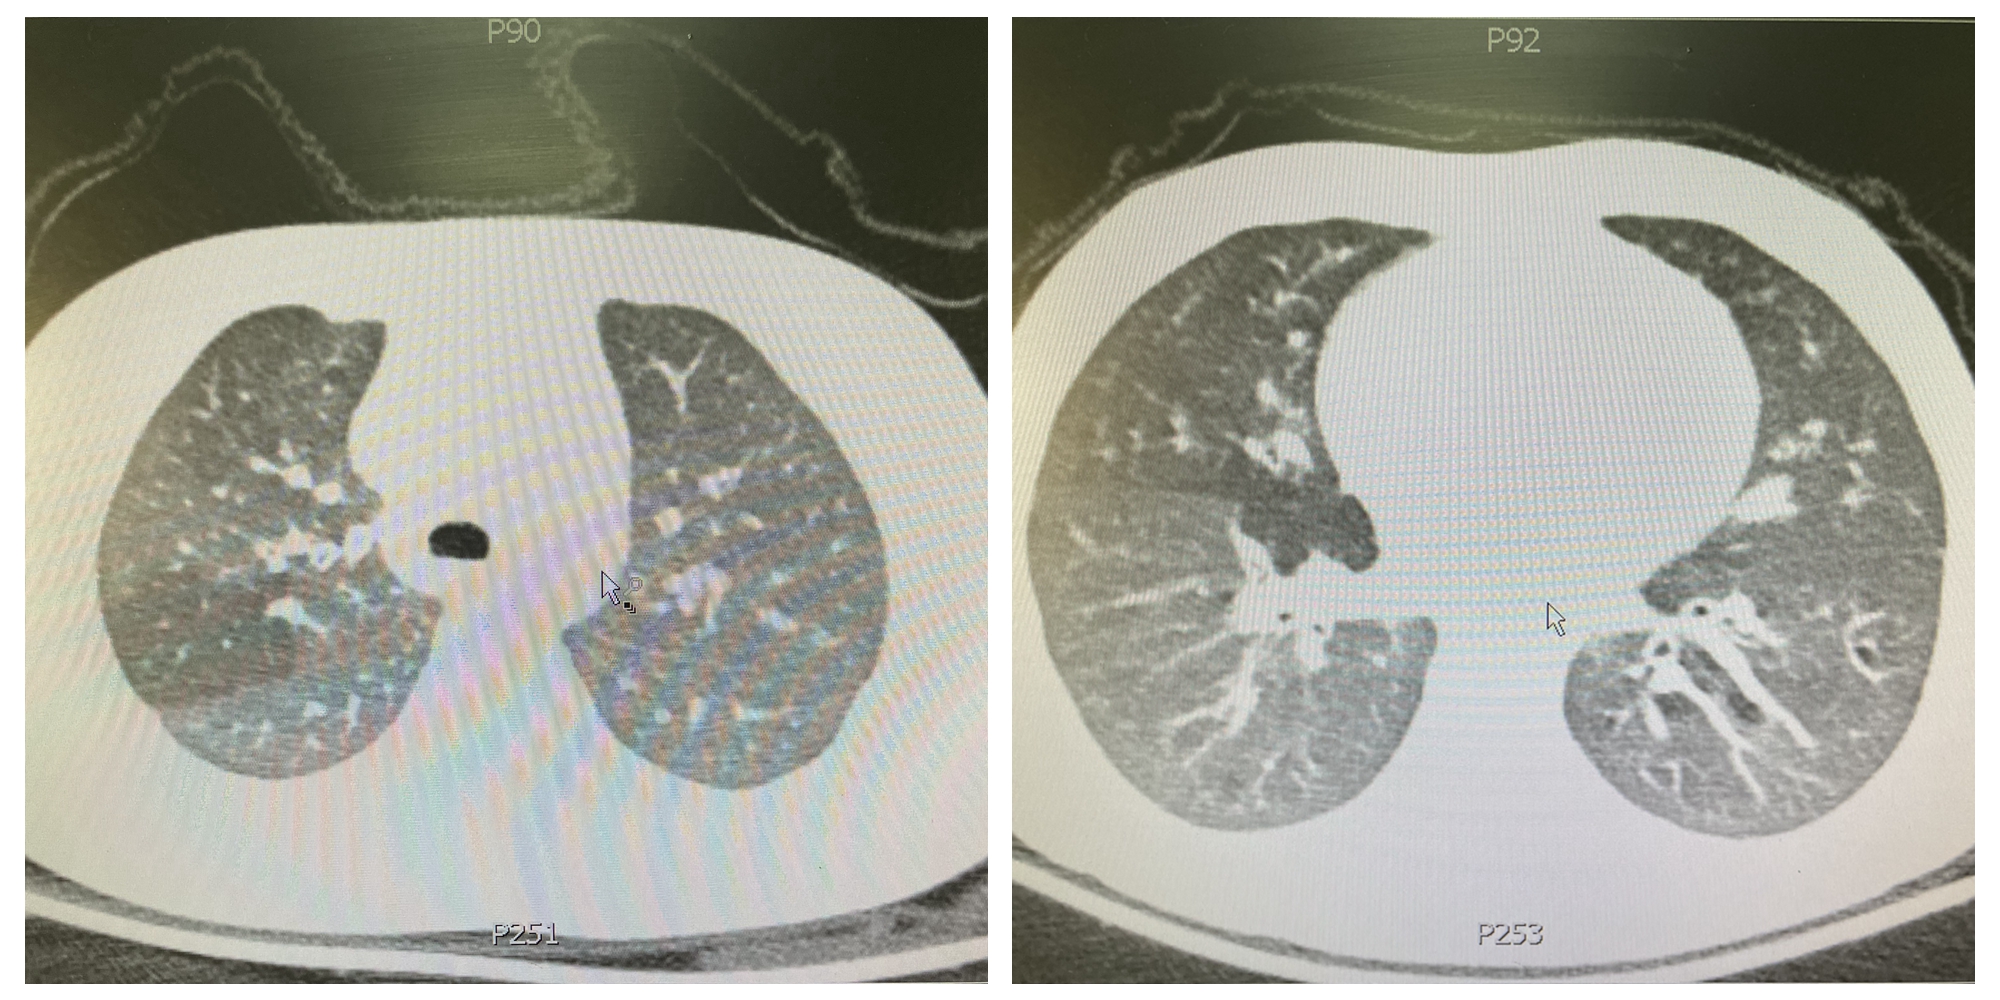

“不,我们还得多考虑一下”。拿到小可胸部CT的结果的罗主任这样说。

在小可的胸部CT上,我们发现了明显的支气管壁增厚和充气不均匀的表现。“小可没有反复哮喘发作和重度哮喘发作的病史”,罗志娟主任提醒大家到:“这不好解释胸部CT为什么会有只有“重症哮喘”病人才会出现的影像学变化。”